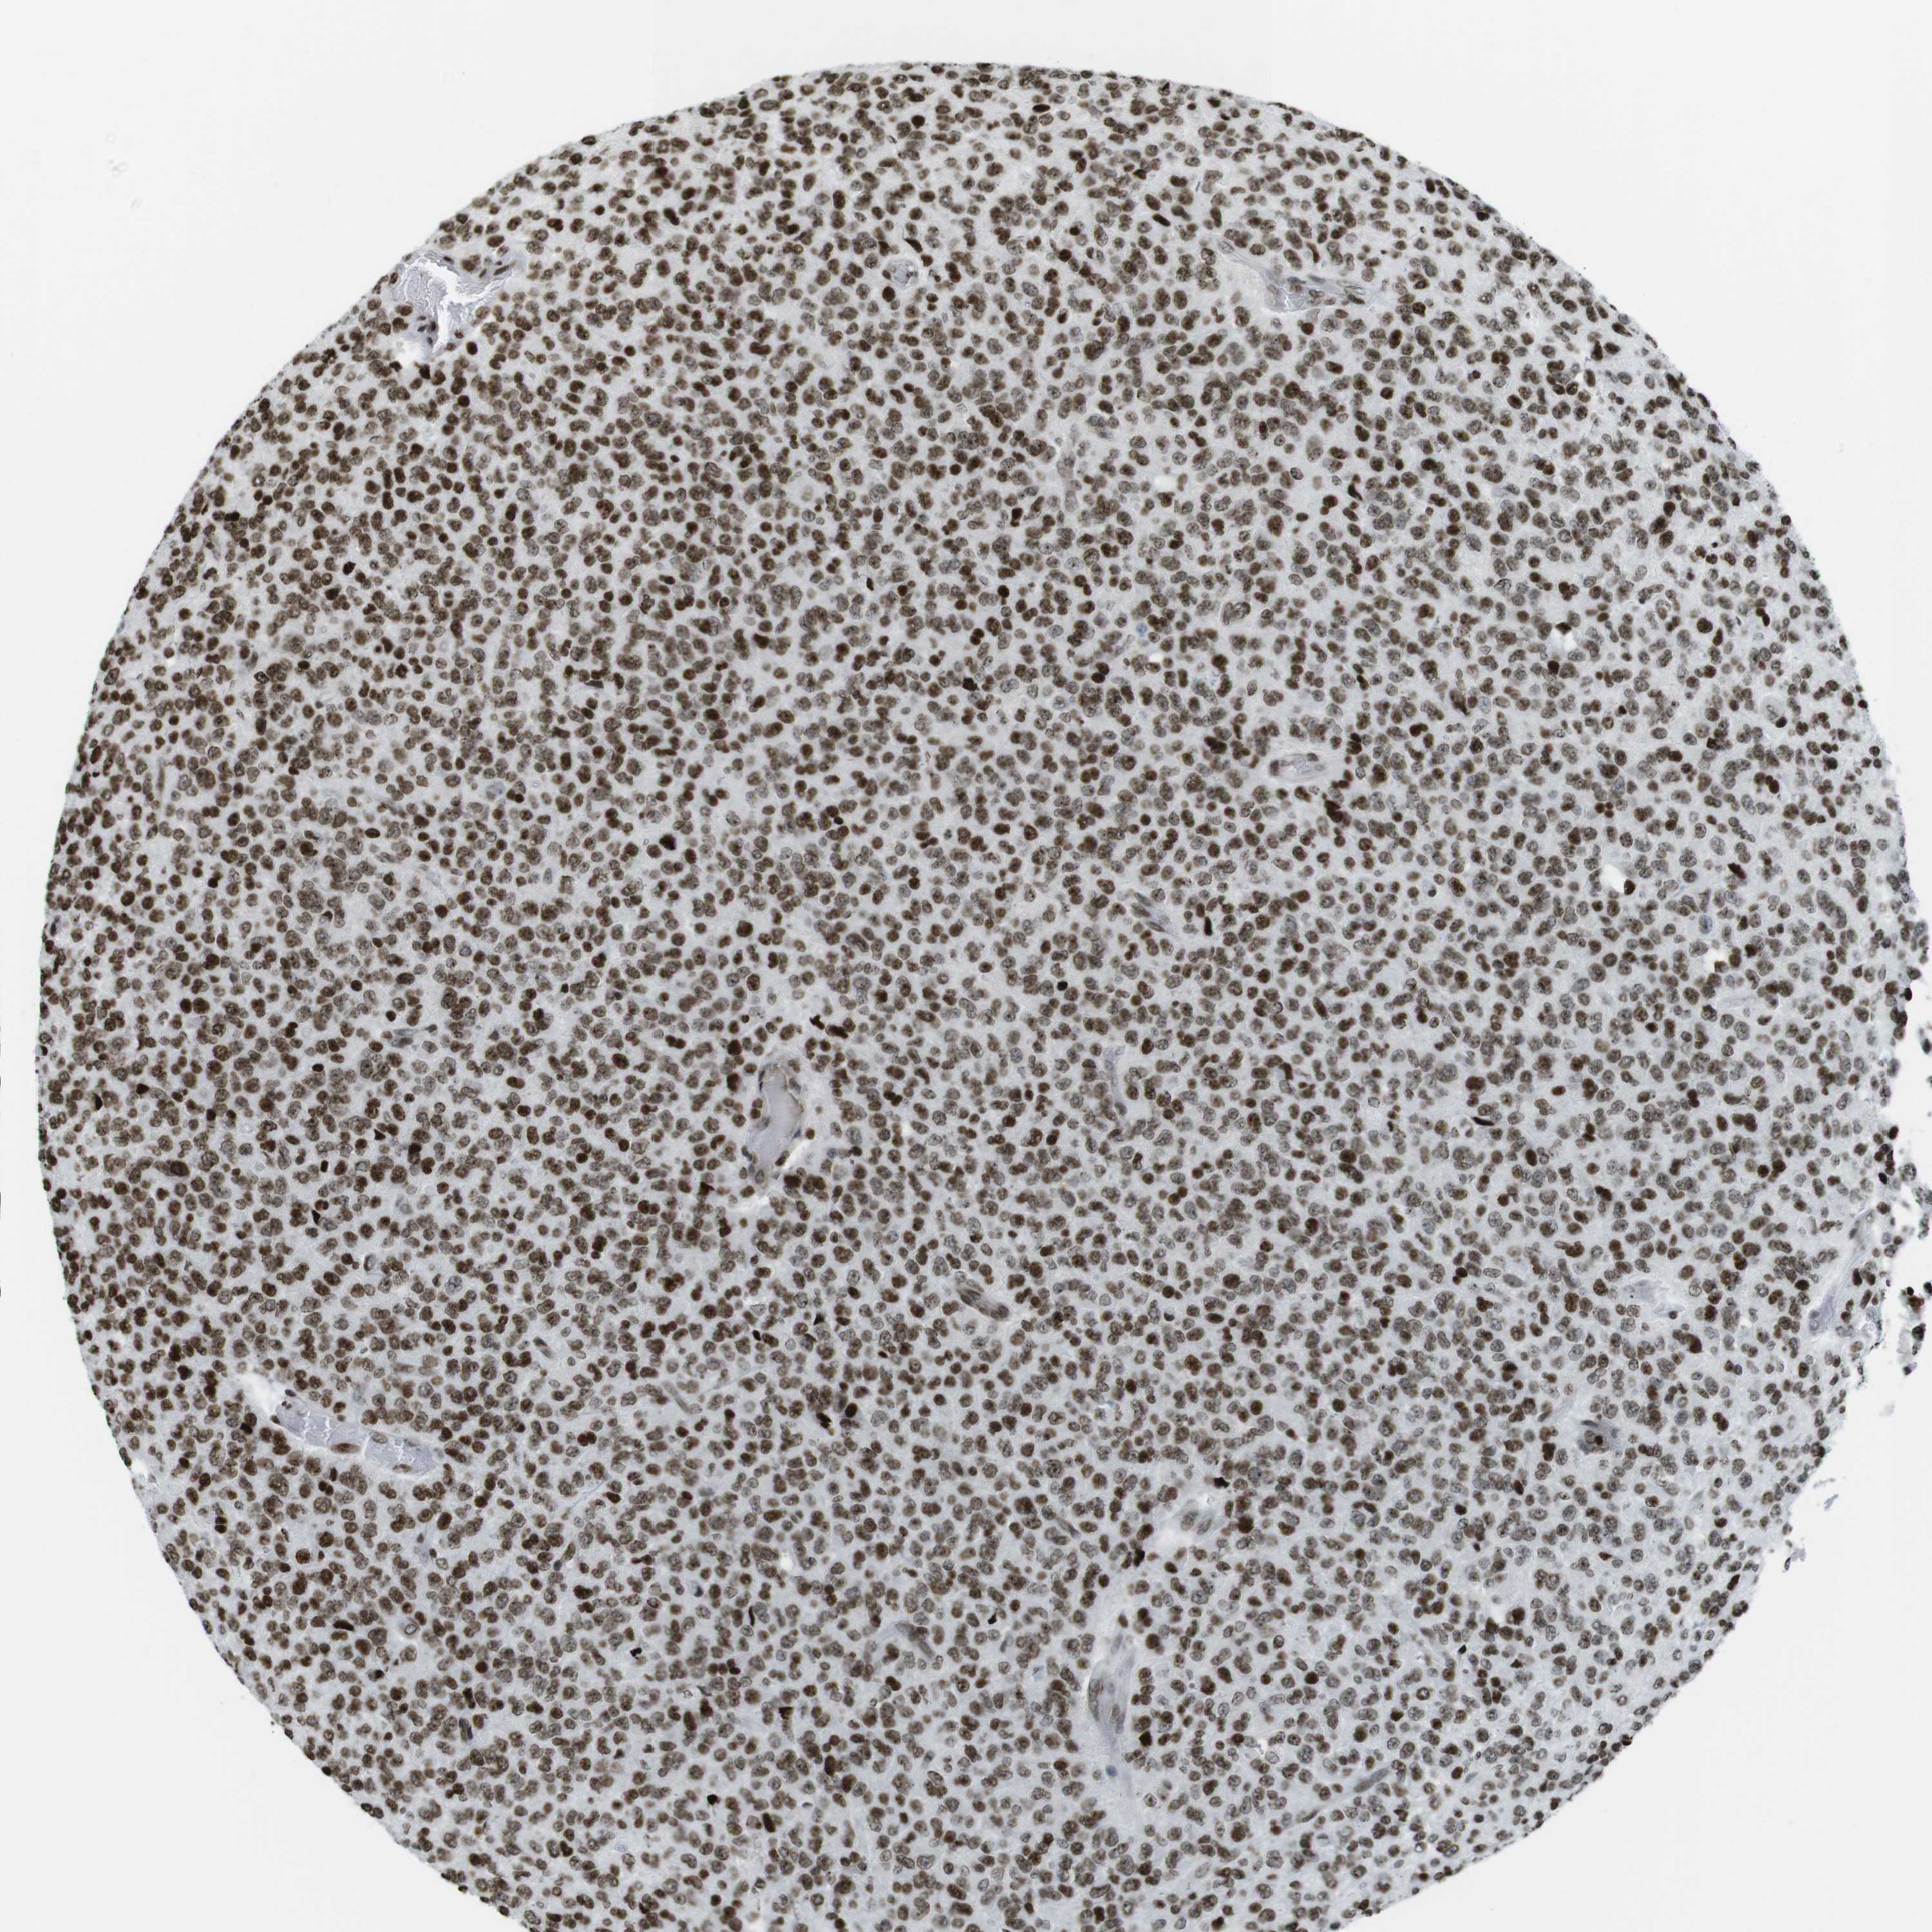

GLIOMA - Protein expressioni

A mouse-over function shows sample information and annotation data. Click on an image to view it in a full screen mode. Samples can be filtered based on level of antibody staining by selecting one or several of the following categories: high, medium, low and not detected. The assay and annotation is described here.

Note that samples used for immunohistochemistry by the Human Protein Atlas do not correspond to samples in the TCGA dataset.

Antibody stainingi

Antibody staining in the annotated cell types in the current human tissue is reported as not detected, low, medium, or high, based on conventional immunohistochemistry profiling in selected tissues. This score is based on the combination of the staining intensity and fraction of stained cells.

Each image is clickable and will lead to virtual microscopy that enables deeper exploration of all samples and also displays staining intensity scores, fraction scores and subcellular localization as well as patient and tissue information for each sample.

Antibody HPA041189

Antibody CAB012242

Staining

High

Medium

Low

Not detected

Intensity

Strong

Moderate

Weak

Negative

Quantity

>75%

75%-25%

<25%

None

Location

Nuclear

Cytoplasmic/membranous

Cytoplasmic/membranous,nuclear

Glioma, malignant, High grade

Glioma, malignant, Low grade